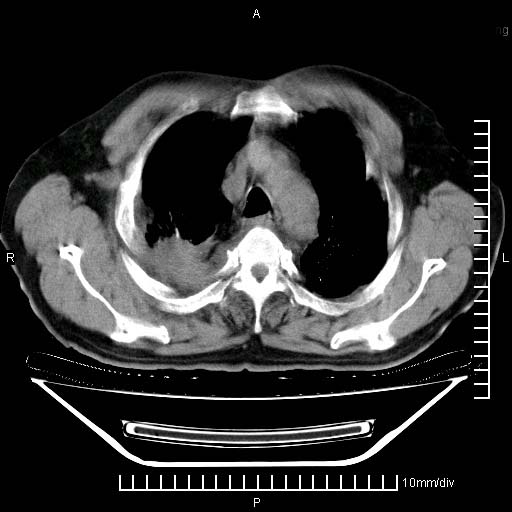

标题: CT24043:胸部增强:男性,60岁

既往肺结核,近10几天,咳嗽,咳痰,右侧胸痛,疼痛较明显,右上肺斑块考虑结核灶胸膜粘连,增强,可惜动脉期没有定好,未见强化,可延迟4分后又见较明显强化,中心见低密度影,如果说结核是边缘强化,可这个灶强化的面积挺大的,让人很挠头。

延迟4分后

强化的组织可能是膨胀不全的肺组织或炎性肉芽组织。

1)两肺继发性肺结核。2)右侧胸膜增厚+少量胸腔积液。